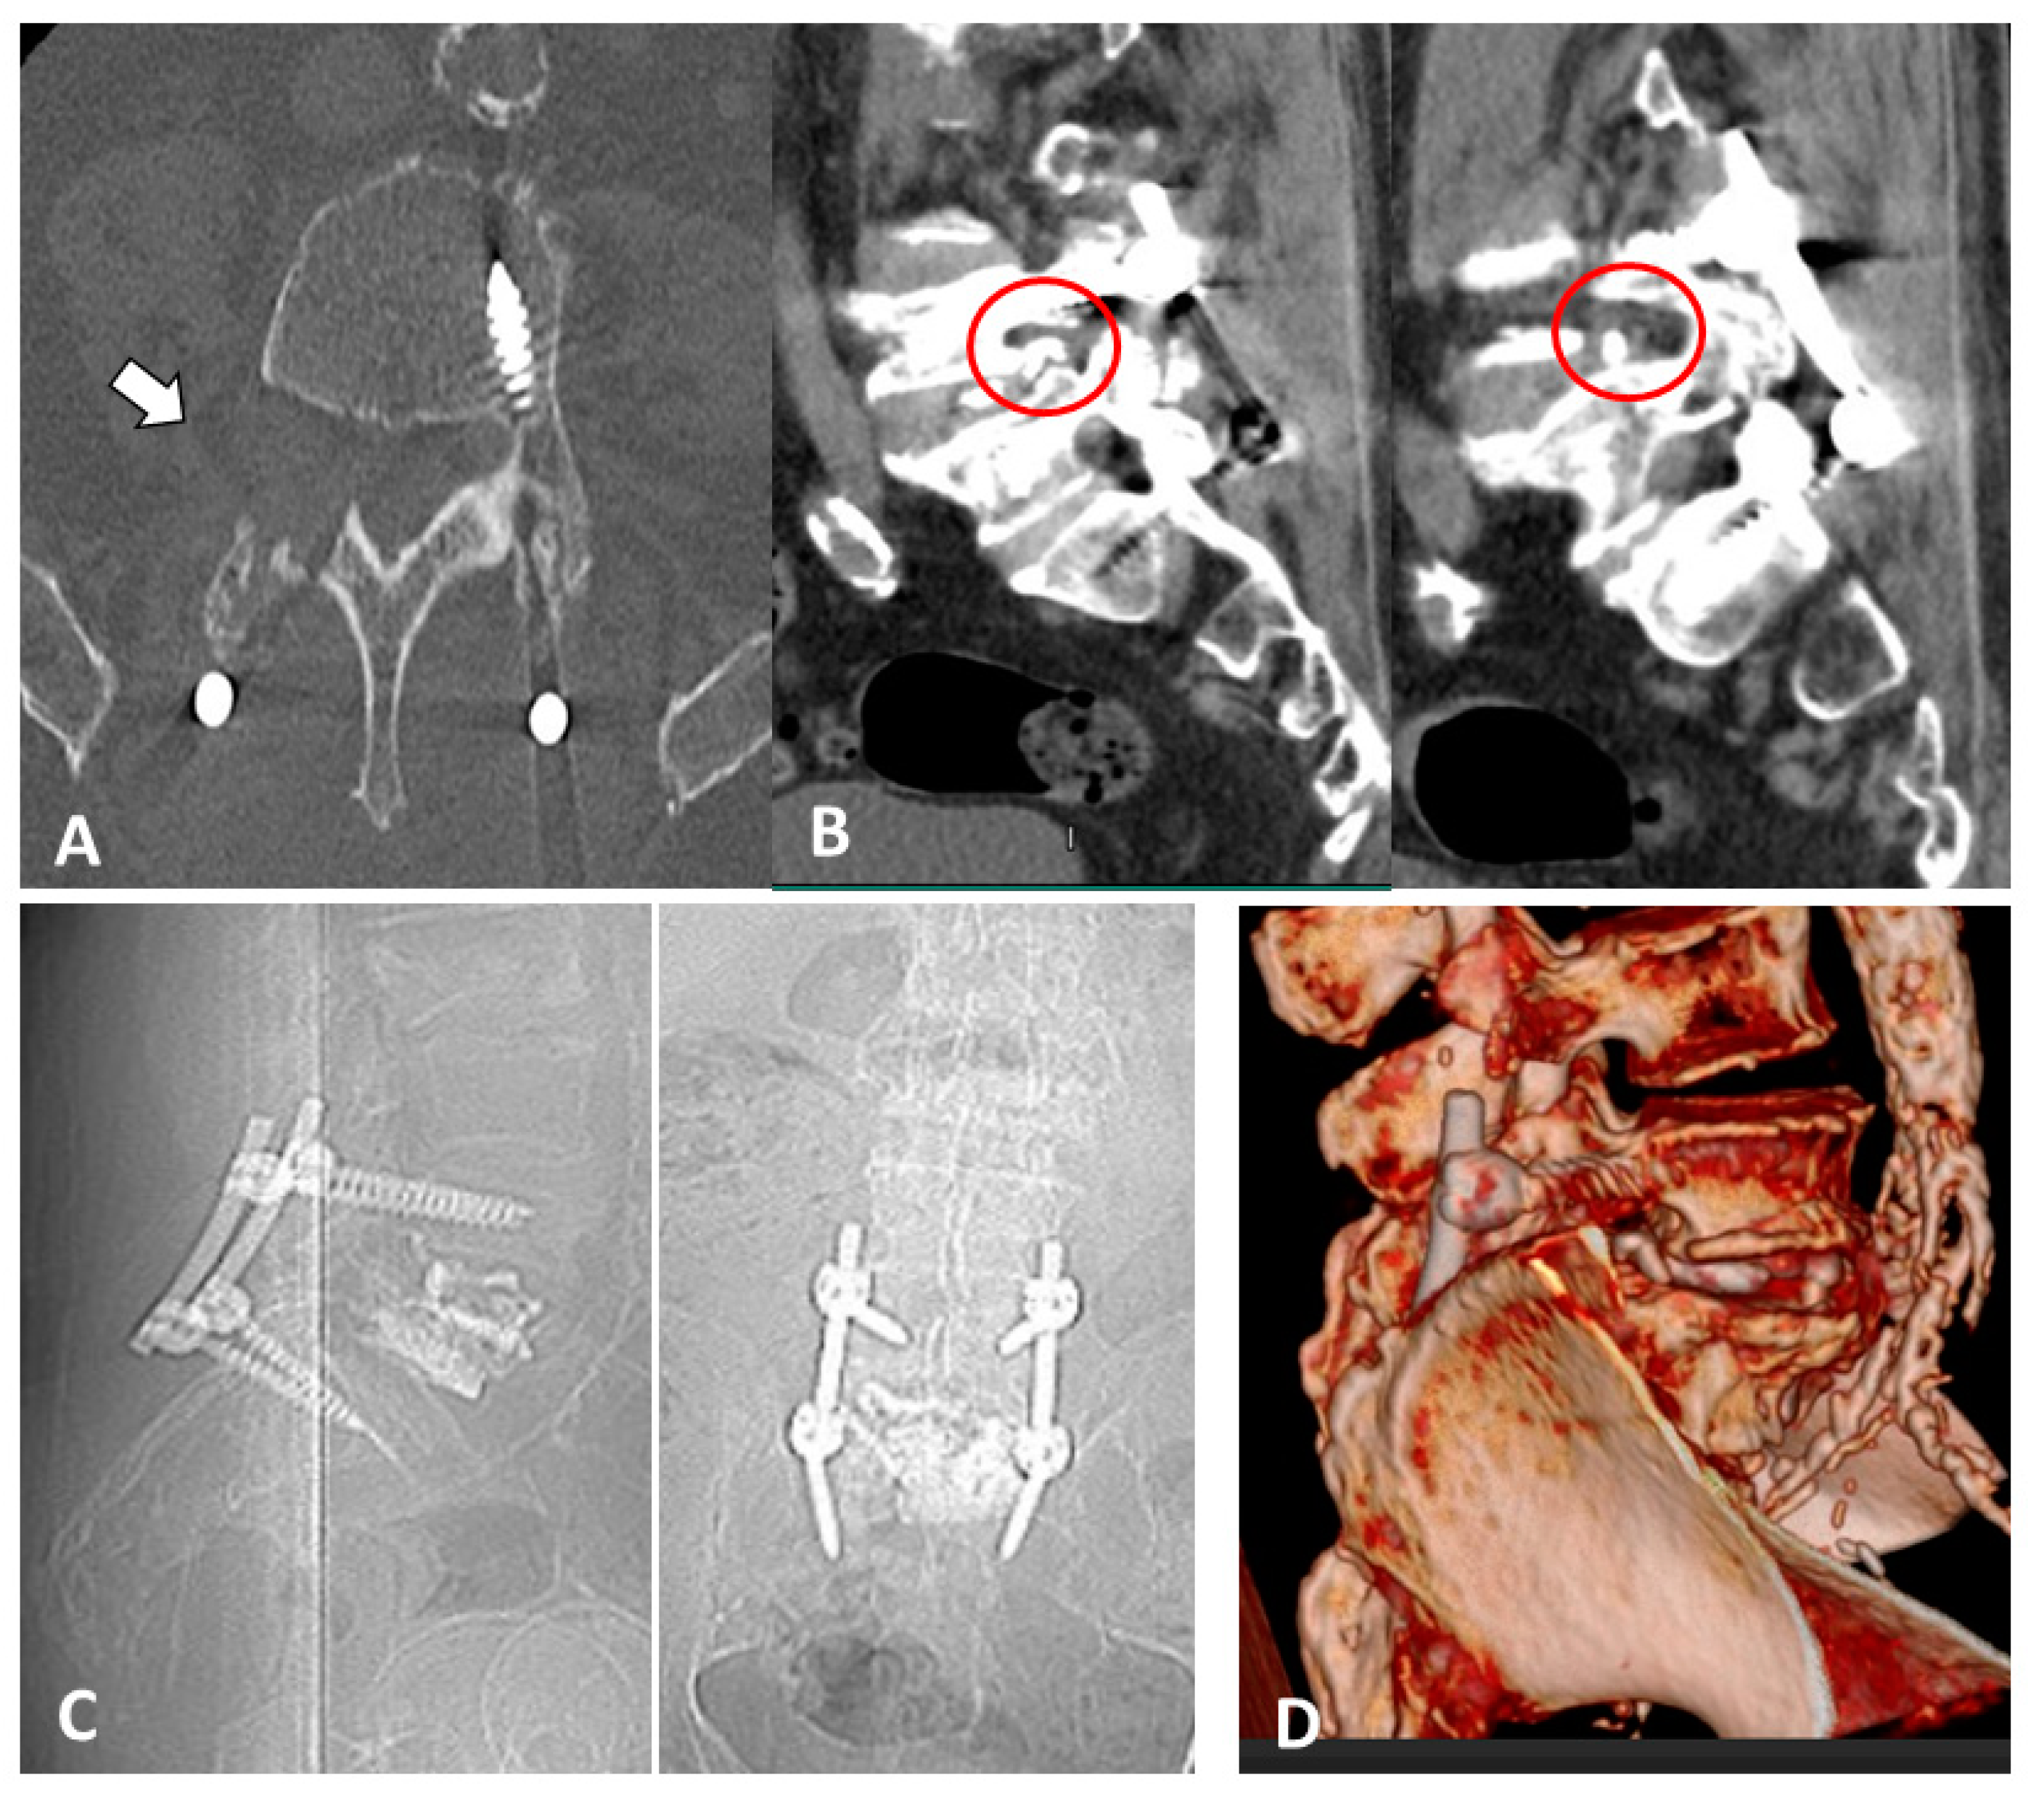

2. Case Report